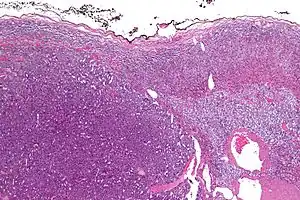

| Micrograph of an adrenocortical carcinoma (left of image – dark blue) and the adrenal cortex it arose from (right-top of image – pink/light blue). Benign adrenal medulla is present (right-middle of image – gray/blue). H&E stain. | |